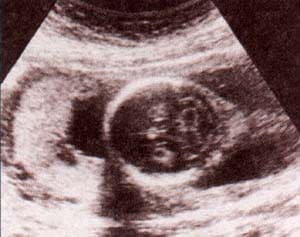

fig. 60. – (b). 25 semanas. corte frontal. es clara la ausencia de calota con tejido cerebral expuesto. |